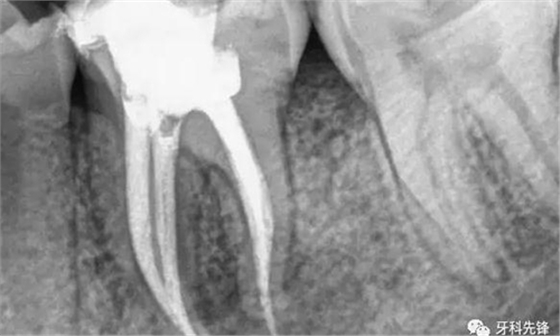

當(dāng)牙齒做完根管治療,由于牙齒自身的結(jié)構(gòu)及治療的需要,牙冠中心一般都是空的,這時(shí),如果直接做牙套,其抗折斷力很差,一般都需要在牙根上打上樁釘,做出個(gè)結(jié)實(shí)的核,以對抗牙齒使用中的折斷力。

對于后牙來說,做完根管治療之后一定要做上牙冠,否則在承受咬合力量時(shí),牙齒容易出現(xiàn)斷裂。少數(shù)做完根管治療的后牙,若是要做單一的牙冠,只需將所剩牙質(zhì)修補(bǔ)足夠,則可不需做樁釘,但若做完根管治療的后牙是要作為假牙的基牙,則無論牙質(zhì)所剩多少,最后都能做好樁釘。